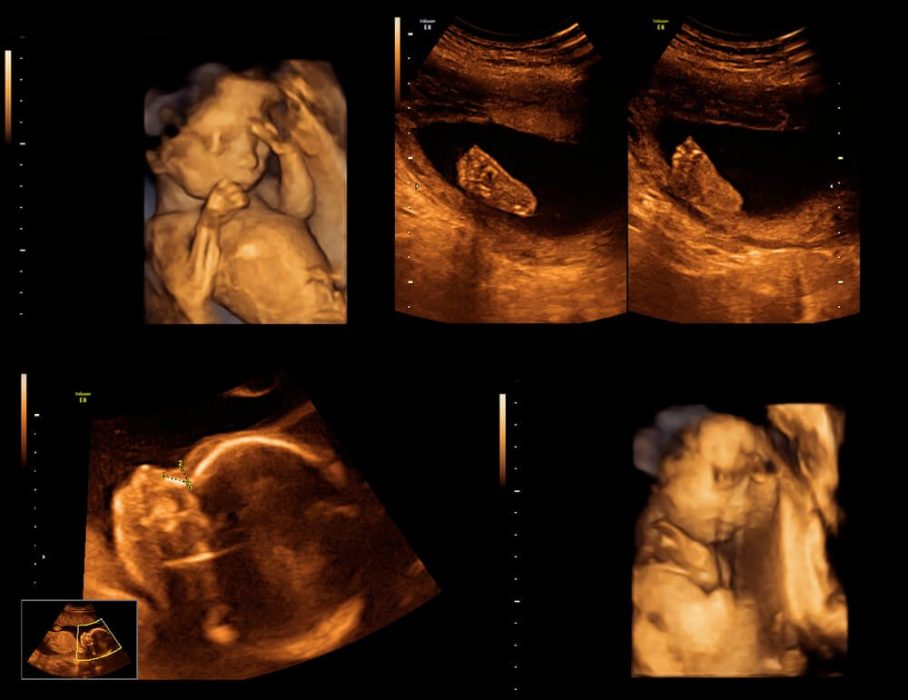

Ayrıntılı ultrasonografide anne karnındaki bebeğin her organı ayrıntılı olarak incelenir. Ayrıca bebeğin suyu, plasenta (bebeğin eşi) değerlendirilir.